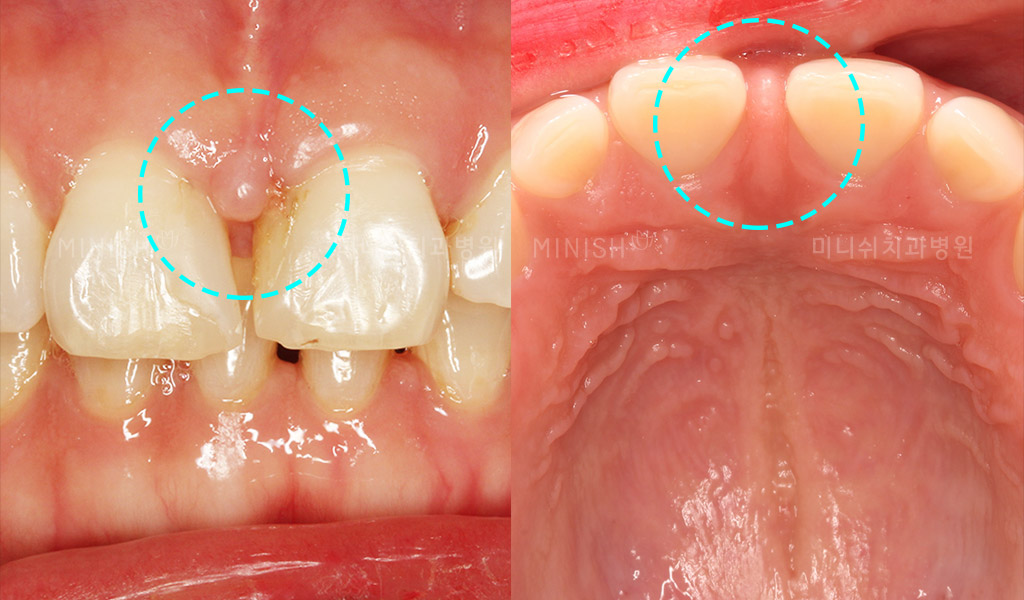

From www.minishteeth.com

Gap In Teeth What causes gap and what options I have? What Causes Gaps In Teeth In Adults There are various ways to close gaps in teeth, which you can read about below. These spaces can form anywhere in the mouth, but are. patients with gap teeth have several options for closing the space between teeth, including braces and invisalign. diastema is a term orthodontists use to describe a gap that exists between two teeth that. What Causes Gaps In Teeth In Adults.